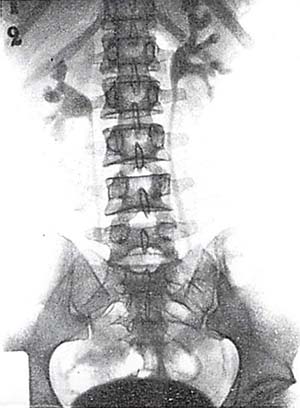

図4. Uroselectanによる排泄性尿路造影.現在の水準から見ても良好な画質である.

【要旨】Binzが抗菌剤として開発したSelectan-Neutralを動物,ついでヒトに投与し,頭痛,嘔気,嘔吐など軽度の副作用をみるのみで安全であることをまず確認した.しかし造影能はまだ不十分であった.Binzが化学構造に手を加えて新たに作り出したUroselectanは溶解性が大きく,充分量のヨードを含み,造影能も良好であった.20ccを3~5分かけて静注し,5~10分後に初回,ついで30分後間隔で2回のX線撮影を行ない,全例において明瞭な尿路造影が得られた.

【解説】前述のように論文発表の優先権を巡る議論の末,研究の直接の担当者であるアメリカ人医師Swickの単著による報告である.供覧されている画像は,現在の排泄性尿路造影と比較しても遜色ないもので,腎盂~尿管~膀胱が明瞭に造影され,水腎症などの病態もよく描出されている(図4).カテーテルを使用せずに尿路系全体を簡便に描出できる検査法の確立は,まさに画期的であった.ただし,Uroselectanの構造,性状などについては全く触れられておらず,これについてはBinzによる後年の総説を待つ必要があった.